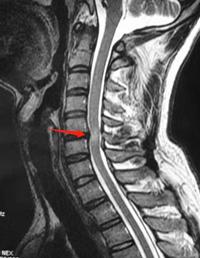

医院给预约了颈椎磁共振,但是需要到2周后才能做,在急诊观察一晚后小陈症状没有加重,于是在给颈椎做颈托固定后就先回家了。回家后小陈继续口服营养神经药,也自己到中医院做针灸,症状没有缓解,手部刺痛加剧,每晚疼痛难熬,难以入睡。小陈经人介绍,慕名前往复旦大学附属中山医院就诊,脊柱外科主任董健教授了解了受伤和诊疗经过,经过仔细体格检查,初步判断小陈是发生了“颈椎过伸伤合并颈脊髓中央管综合征”,立马给联系了当天颈椎磁共振来明确诊断。和董教授的判断一致,小陈原来有颈56的椎间盘突出,外伤后导致了脊髓的损伤。(如下图所示)

颈56椎间盘突出,后方脊髓内有水肿信号